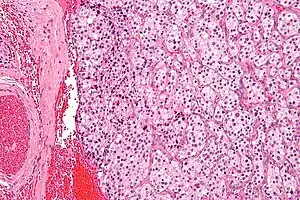

![]() Section of part of human carotid body. Highly magnified. Numerous blood vessels are seen in section among the cells. | |

The carotid body is a small cluster of peripheral chemoreceptor cells and supporting sustentacular cells situated at the bifurcation of each common carotid artery in its tunica externa.[1][2]

The carotid body is made up of two types of cells, called glomus cells: glomus type I cells are peripheral chemoreceptors, and glomus type II cells are sustentacular supportive cells.